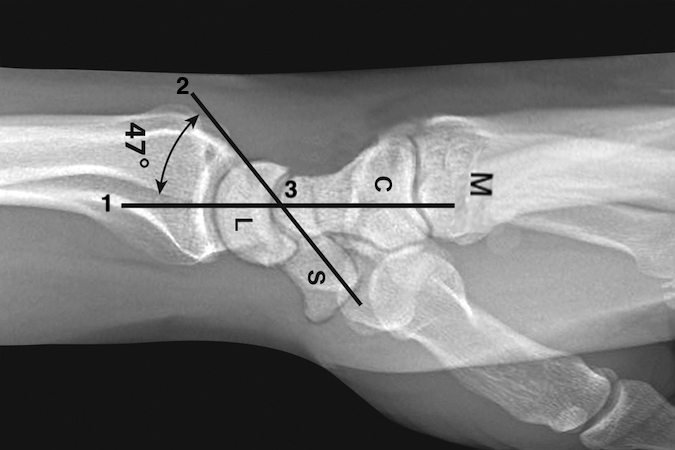

• X-rays can be very helpful when assessing carpal area injuries. On a normal neutral rotation lateral, the horizontal axis of the radius, lunate, capitate, and metacarpals is a straight line (1). A line (2) the longitudinal axis of the scaphoid crosses line (1) at point (3). The average normal angle between these lines is 47° (range 30-60°). Angles outside this range suggest carpal instability (DISI >60°; VISI <30°).

X-rays can be very helpful when assessing carpal area injuries. On a normal neutral rotation lateral, the horizontal axis of the radius, lunate, capitate, and metacarpals is a straight line (1). A line (2) the longitudinal axis of the scaphoid crosses line (1) at point (3). The average normal angle between these lines is 47° (range 30-60°). Angles outside this range suggest carpal instability (DISI >60°; VISI <30°).